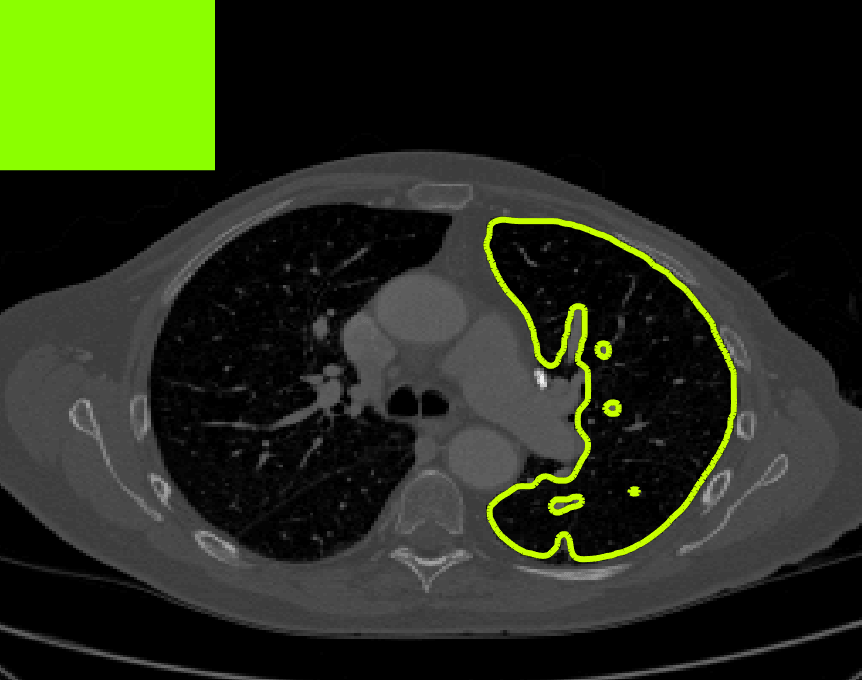

The motivation for this work comes from observing contradictions in using piecewise-constant intensity fitting terms in selective segmentation. Whilst good results are possible with this approach, the exceptional cases lead to severe limitations in practice. This is quite common in medical imaging as demonstrated in Fig. 1, where the target foreground has a low intensity. Given that the corresponding background includes large regions of low intensity, the optimal average intensities for this segmentation problem are and . For cases where , we see that by (1), almost everywhere in the domain . This means that it is very difficult to achieve an adequate result, without an over-reliance on the user input or parameter selection.

for and as defined in (33). This is consistent with respect to the intensities of the observed object and the concept of selective segmentation. In Fig. 3 we see the difference between CV and the proposed fitting terms for given user input on a CT image. For the CT image, the CV fitting terms are near 0 within the target region. This is despite there being a distinct homogeneous area with good contrast on the boundary. This illustrates the problem we are aiming to overcome. With the proposed fitting term this phenomenon should be avoided in cases like this. By defining as in (33) there is no contradiction if the foreground and background intensities of the target region are similar.